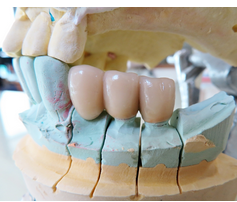

- 임플란트 복원: 임플란트가 안정적으로 고정되면 인공 이빨이 부착됩니다. 이 단계에서는 임플란트를 지지할 구조물인 프레임이나 초록색 인상물 등을 설치하고, 세라믹, 금속, 합금 등으로 만들어진 인공 이빨을 부착합니다.